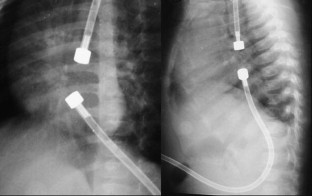

Between September 2001 and March 2004, five children were selected for treatment. Two of the children had esophageal atresia without fistula (type A) and three had atresia with fistula converted to type A surgically; however, surgeons failed to achieve an anastomosis because of the width of the gap. Neodymium-iron-boron magnets were used. Daily chest radiographs were taken until union of the magnets was observed. They were then replaced with an orogastric tube.

Anastomosis was achieved in all patients in an average of 4.8 days. One patient, with signs of early sepsis, was successfully treated with antibiotics. In four of the five patients, esophageal stenosis developed. At the time of this report, two patients were free of treatment and on an oral diet (after 26 months), two patients required periodic balloon dilatation, and one patient had recently undergone surgery due to recurrent esophageal stenosis not amenable to balloon dilatation.

Fig. 2